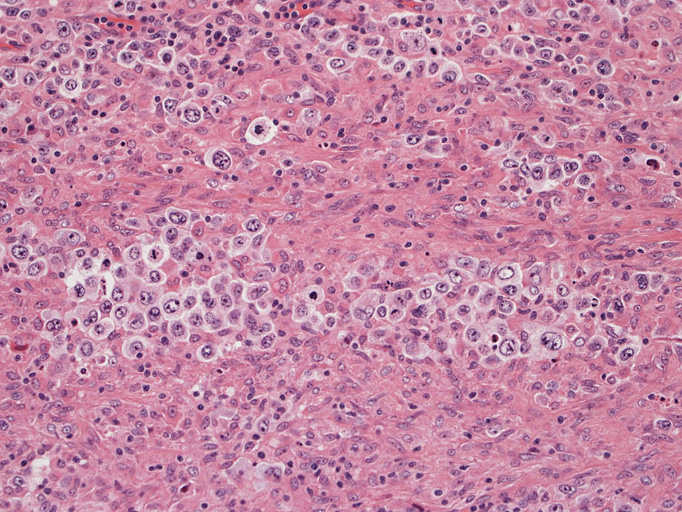

光顕および免疫染色所見

結節構造内では, 好酸性細胞質をもつ組織球の増生を背景に大型異型細胞が散在性または集蔟して増殖している。被膜下にも線維化組織内にbizzarreな大型細胞が認められる。リンパ球は小型リンパ球が大型異型細胞を含む組織球性の結節辺縁に存在する。大型細胞は, centroblastic cellが多く, その他 Hodgkin cell-like cell, RS細胞様巨細胞, 腎臓型の核をもった細胞, 多型核の細胞など多彩な形態を示す。異型核分裂像をふくむ核分裂像が多い。